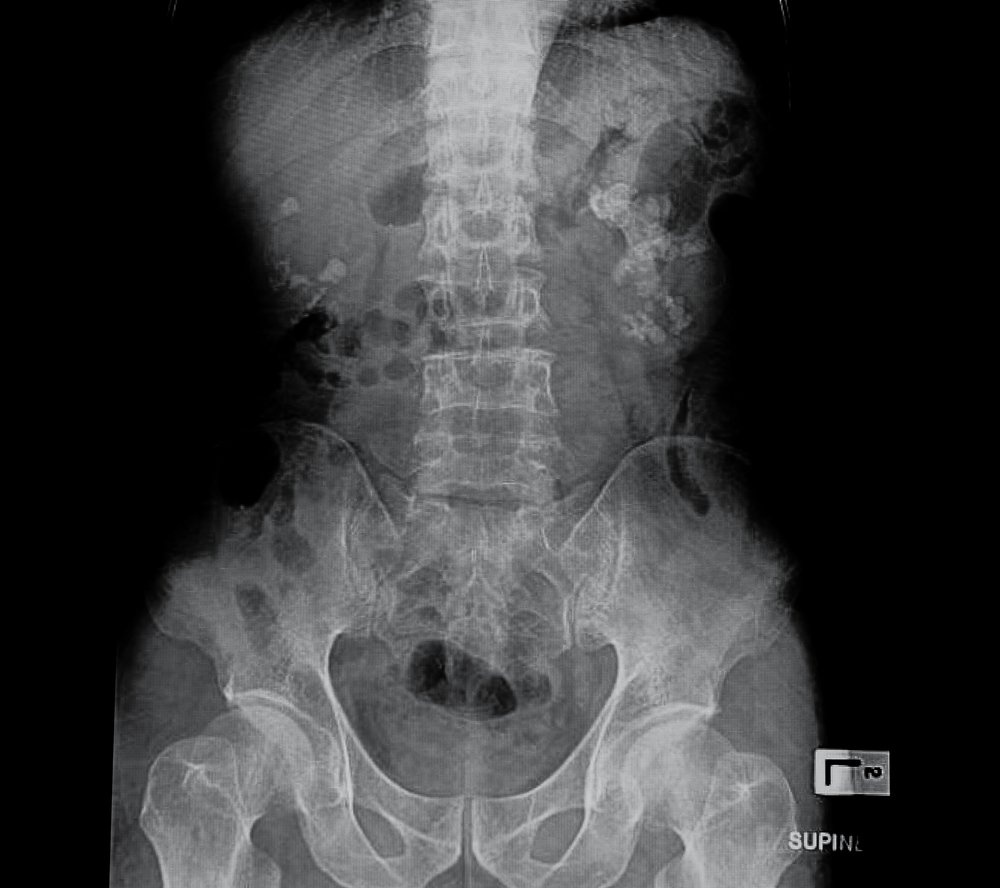

| Dễ bị sỏi thận: Chế độ ăn quá nhiều protein có thể gây tổn hại cho thận. Protein có nguồn gốc động vật chứa nhiều một hợp chất gọi là purin, có thể phân hủy thành axit uric. Quá nhiều axit uric sẽ làm tăng nguy cơ bị sỏi thận. Hầu hết mọi người sẽ không gặp khó khăn để phá vỡ protein trong cơ thể. Tuy nhiên, những người có tiền sử gia đình bị thận nên thận trọng khi ăn nhiều thịt. |